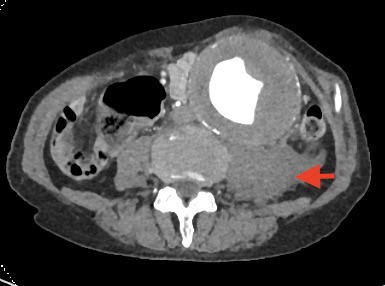

偶然发现左肺门占位:中央型肺癌?

腹主动脉瘤破裂,后腹膜血肿。管腔呈新月型是特征性表现。瘤体最大直径约9cm。